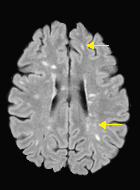

We observed that memberships predicted with an FC layer result in more false positives compared to a fully convolutional network. An example is shown in Fig. 2, where lesion memberships are generated from MPRAGE and FLAIR using the proposed model of convolutional pathways and a comparable model where the last convolutional pathway after concatenation (see Fig. 1) is replaced with a FC layer predicting voxel-wise memberships. The membership image generated with an FC layer, although being close to inside the lesions, has high values () in the left and right frontal cortex where the FLAIR image shows some artifacts. However, the membership obtained with the proposed method shows relatively low values near the frontal cortex.

With FC layer, voxel-wise predictions are performed for each voxel on a new image. Therefore the prediction time for the whole image comprising millions of voxels can take some time even on a GPU, as mentioned in Wachinger et al. (2017). In contrast, with fully convolutional prediction, lesion membership estimation of a mm3 MR volume of size takes only a couple of seconds. Note that although patches are used for training, the final trained model contains only convolution filters and does not depend in any way on the input patch size. Therefore during testing, the lesion membership of a whole 2D slice, irrespective of the slice size, is predicted at a time by applying convolutions on the whole slice. Without an FC layer, the images need not be decomposed into sub-regions, e.g., Kamnitsas et al. (2017). Consequently, there is no need to employ membership smoothing between sub-regions. In addition, since the training memberships, generated by Gaussian blurring of hard segmentations, are smooth, the resultant predicted memberships are also smooth (Fig. 2 last column).